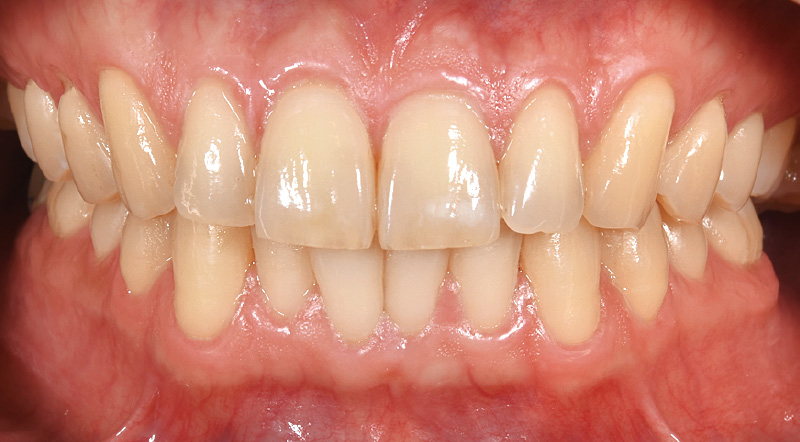

こうしたフルマウスの症例の場合、補綴装置の精度を高めることが重要です。この患者さんは顎位に大きな乱れがないため、機能回復を急ぐべきだと判断し、デジタル技術を活用した治療を選択しました。最終的に調整の頻度が少なく精度の高い補綴装置の製作に注力しました。補綴治療計画の際に、特に意識しているのが歯頸ラインの形態と清掃性です。この症例ではプロビジョナルレストレーションの装着期間中、担当歯科衛生士が歯間ブラシが通るか、磨きにくい箇所はないかなどを細かく確認し、そのフィードバックをもとに歯科技工士と設計の修正を重ねました。見た目に美しく、機能的にも優れた補綴装置を作製するためにはこうしたプロセスが重要なのです。

![[写真] 写真左:プロビジョナルレストレーションをステージごとに装着し、審美性や清掃性を意識した形態を模索 写真右:2022年プロビジョナルレストレーションの形態を踏襲し、最終補綴を装着](/academic/dentalmagazine/wp-content/uploads/sites/2/2026/04//196-12_photo04.jpg)

症例1-4 写真左:プロビジョナルレストレーションをステージごとに装着し、審美性や清掃性を意識した形態を模索。写真右:2022年プロビジョナルレストレーションの形態を踏襲し、最終補綴を装着。 -